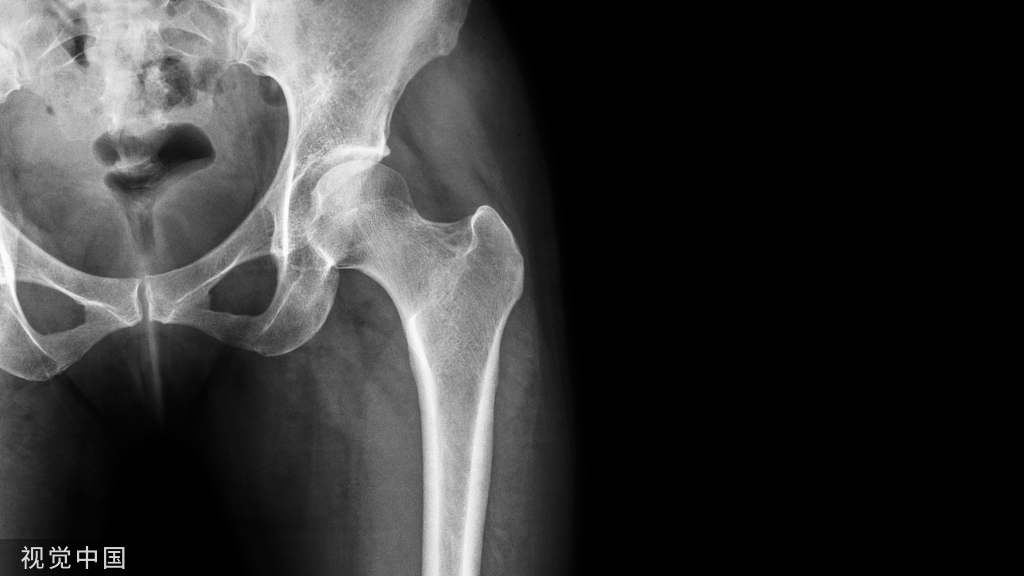

骨关节炎(OA)最常见的临床症状为关节疼痛、关节活动受限,压痛、关节畸形是手部OA和膝关节OA最常见的体征,骨摩擦音(感)、肌肉萎缩常见于膝关节OA。